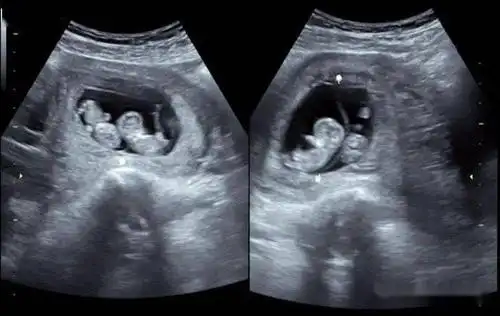

双胎妊娠超声检查小问答_绒毛